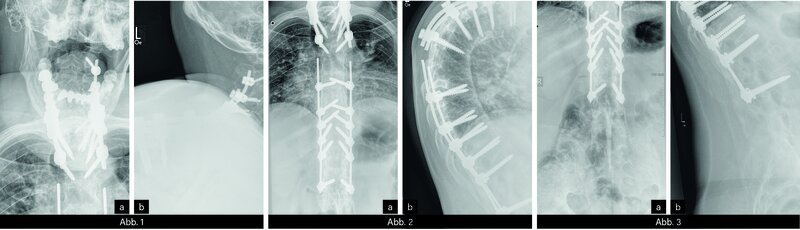

KLINISCHER BEFUND: 165 cm (1993 bei Musterung 178 cm) 101 kg, Wirbelsäulenstatus: HWS – Rotation 0-0-0°), Traguswandabstand 25 cm, BWS – Thoraxumfang Inspiration/Exspiration Differenz 0 cm, LWS – Schober lumbal 10/12 cm. Finger-Boden-Abstand 39 cm. Kein Druckschmerz im ISG-Bereich. Reizlose Narben bei Z. n. zweimaliger Aufrichtoperation.

BILDGEBENDE DIAGNOSTIK: Röntgen (s. u.)

DIAGNOSE: Fortgeschrittene AS mit Z. n. zweimaliger Aufrichtoperation

Die AS ist eine chronische Entzündung der kleinen Wirbelgelenke aus dem rheumatischen Formenkreis. Sie gehört zur Gruppe der seronegativen Spondylarthritiden. Die bevorzugte Manifestation der Systemerkrankung liegt im Bereich der kaudalen Wirbelsäule und der Iliosakralgelenke (ISG). Als bildgebende Diagnostik wird im Frühstadium der Erkrankung die MRT eingesetzt. Nach monatelanger Krankheitsdauer können radiologisch typische, z. T. pathognomonische Befunde erhoben werden. Frühzeitige radiologische Hinweise auf eine AS sind dünne vertikale Syndesmophyten und eine begleitende bilaterale Sakroiliitis. Ferner kommt es zu einer diffusen Osteopenie des Achsenskeletts. Im Endstadium versteift sich die gesamte Wirbelsäule bambusstabförmig und es kommt zur Kastenwirbelbildung. Die kyphotische Fehlstellung führt zum Totalrundrücken. Im fortgeschrittenen Stadium ist als operative Therapieoption eine chirurgische Aufrichtoperation möglich.